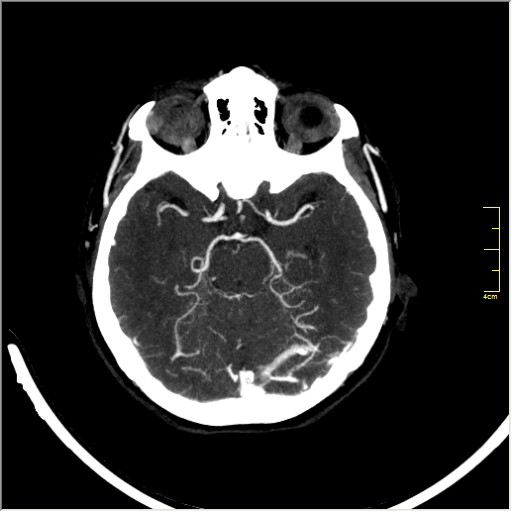

КТ ангиография головного мозга

Стандартная процедура в современной работе КТ кабинета, весьма несложна в исполнении.

Сканы представленны в режиме MIP.

Angio0.JPG

Angio1.JPG

Angio2.JPG

Angio3.JPG

Angio4.JPG